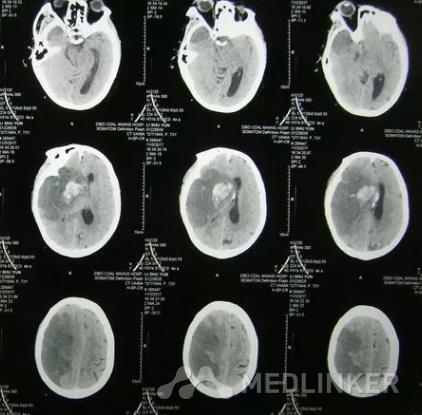

查体:血压150/110 mmHg,神清,脑神经(-),四肢肌力、肌张力正常,左上肢腱反射亢进,余肢体腱反射活跃。血沉、肝肾功能、电解质、糖化血红蛋白均正常。头颅MRI检查,DWI可见右侧顶叶点状高信号影,新发脑梗死可能。头颈部CTA检查提示右侧颈内动脉起始处重度狭窄。

诊断:右侧顶叶脑梗死 治疗:予阿司匹林抗血小板、阿托伐他汀调脂,以及依达拉奉清除氧自由基。同时给以复方曲肽注射液等对症支持治疗,改善患者凝血功能和微循环障碍,促进患者恢复。治疗3d后,患者症状明显缓解。